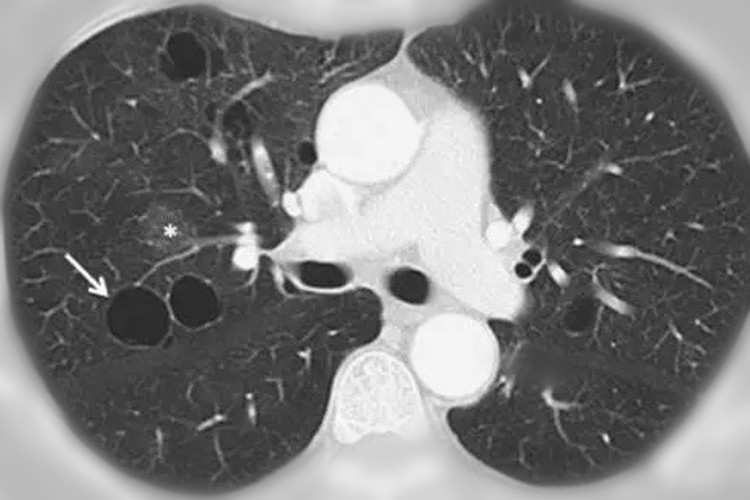

这些肺泡是很小的,即便做胸部CT也是看不到的,但是如果在某种原因的作用下,肺泡腔的压力增高,那肺泡内壁就会破裂。

破裂的肺泡会相互融合,这样的话就会形成比原来肺泡更大的囊腔,也就是我们说的肺大疱。

不过需要注意,肺大疱的直径一般来说是大于1cm的,而且里面还含有一些气体。

说白了,肺大疱就是一种含有气体的空腔,较小的单个肺大疱一般来说都没有明显的症状。